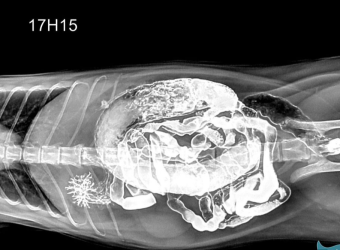

X-quang ổ bụng chó mèo tại Sing Pet Biên Hòa, Đồng Nai. Chẩn đoán nhanh, chính xác, phát hiện dị vật, tắc nghẽn, u ổ bụng, hỗ trợ điều trị và theo dõi hậu kiểm hiệu quả.